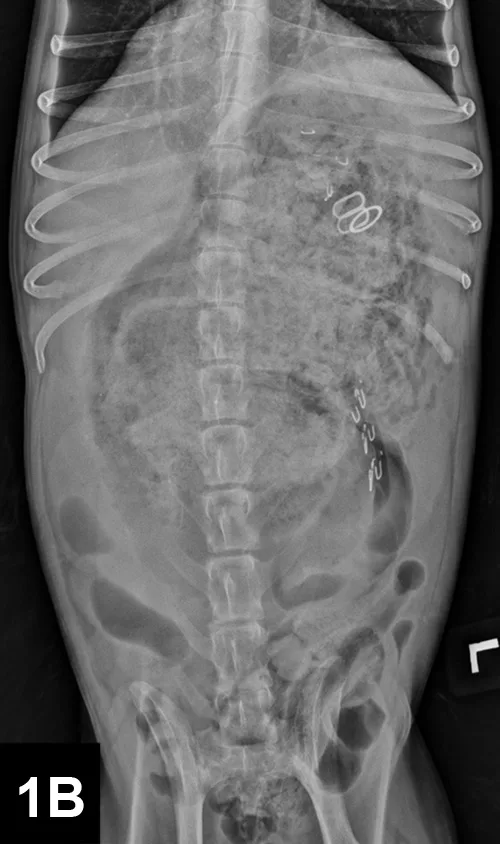

Abdominal Radiography: Right lateral (Figure 1A, above) and VD views (Figure 1B) of the abdomen were obtained.

Radiographic Findings: The right lateral view (Figure 2) showed severe gastric distension (white double headed arrow) with granular ingesta, intermediate opacity oval structures seen in the ventral stomach on the lateral view (suggesting rubber bands or hair elastics), and various metallic structures (compatible with bra straps and hooks). The small and large intestines are displaced caudally by the gastric distension. The gas-distended small intestine (white bar) measured up to 24 mm and the height of the L5 vertebral body (black bar) was 11 mm; this gives a small intestinal to L5 ratio of 2.2, which is much greater than the upper limit of 1.6 for normal small intestine to L5 height ratio.1